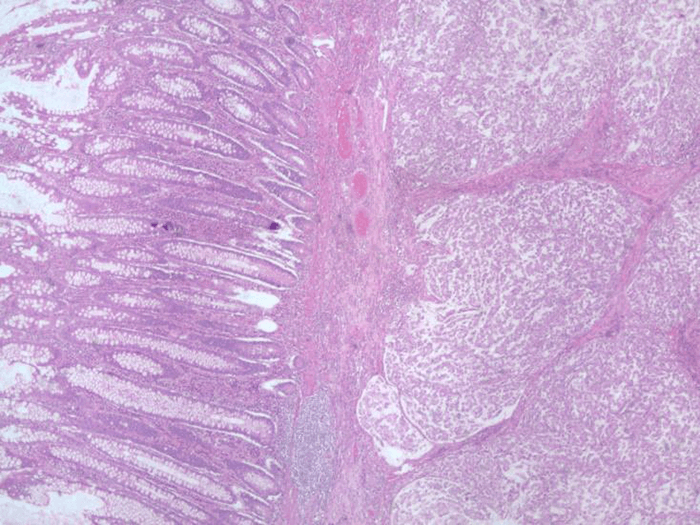

The patient is a 75-year-old man who presented epigastric pain, diarrhea, and passage of melanotic stool for two weeks. He reported no weight loss and had no prior history of cancers nor a family history of cancer. In view of his symptoms, he underwent an esophagogastroduodenoscopy and colonoscopy that revealed gastritis and a large ulcerated mass in the ascending colon respectively. Biopsies of the colonic mass were reported as goblet cell carcinoid. Staging CT scans of the chest, abdomen and pelvis revealed the colon mass, but were negative for metastasis. Initial carcinoembryonic antigen (CEA) was Figure 1. Hematoxylin and eosin stain of primary goblet cell carcinoid tumor in ascending colon. Fourteen lymph nodes were harvested, and all were negative for metastasis (Stage T4N0M0). The tumor was positive for neuron specific enolase (NSE) (Figure 2) and synaptophysin (Figure 3), but chromogranin A and CD56 negative. Histological examination of the appendix was normal (Figure 4). 15 ng/mL and chromogranin A levels was 1335ng/mL. He underwent a laparoscopic right hemicolectomy.

Pathologic examination revealed a 5 cm ulcerating mass extending into the subserosa of the ascending colon. Microscopically, the tumor demonstrated goblet cells arranged in an organoid fashion (Figure 1) with a mitotic index of 5/mm3 and a Ki-67 labeling index of 60%. It was assigned a Tang B classification.

Figure 1. Hematoxylin and eosin stain of primary goblet cell carcinoid tumor in ascending colon.